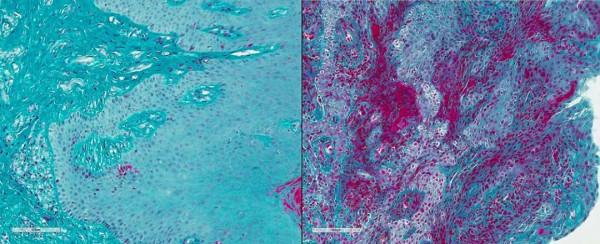

研究人員在牙周炎患者的牙齦組織中也發現了同樣高水平的纖維蛋白沉積和中性粒細胞浸潤,而健康人中則幾乎沒有。

健康人(左)和牙周炎患者(右)牙齦組織中纖維蛋白(紅色)的沉積對比